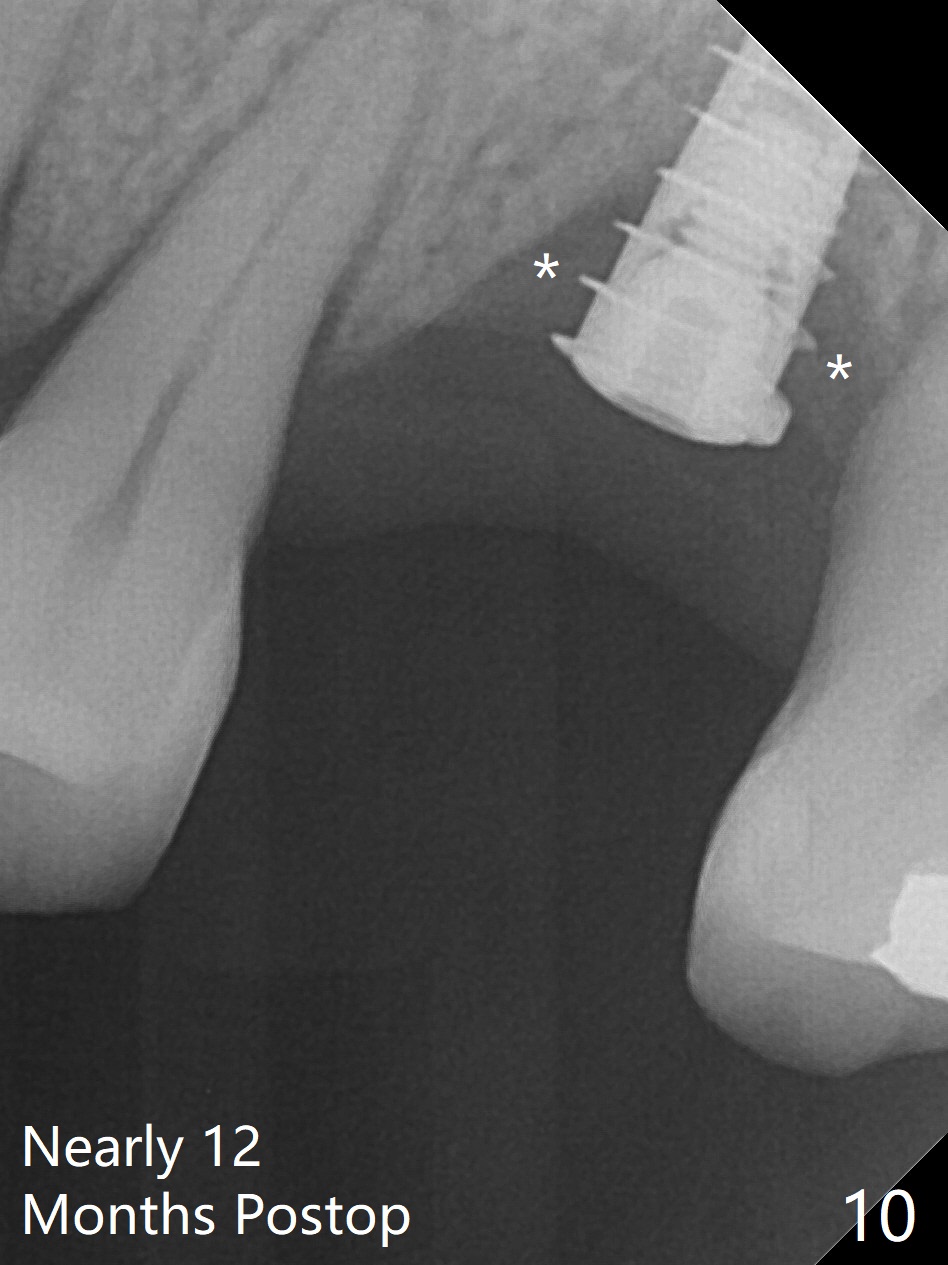

Preop exam shows the narrow ridge at #14. Magic split is used for access and initiation of osteotomy and bone expansion, followed by 3 mm Magic Expander for 11 mm (ME, Fig.1 (yellow line: sinus floor)). In fact the bone is soft. After use of 3.8 mm ME and Lindamann bur (to move the osteotomy distobuccally), a 4x11 mm dummy implant is placed with 20 Ncm (Fig.2). Following use of Lindamann bur for the same purpose as mentioned above, a 4.5x9 mm IBS implant is placed 3 mm subgingival with <30 Ncm (Fig.3,4). Bone graft is placed for sinus lift prior to implantation. A 5x3 mm healing abutment is placed. Bone loss is minimal 3.5 months postop (Fig.5) and striking 8 months postop (after crown cementation, Fig.6-8). The bone loss persists in spite of crown and abutment removal (Fig.9,10). Bone graft or implant redo is planned.